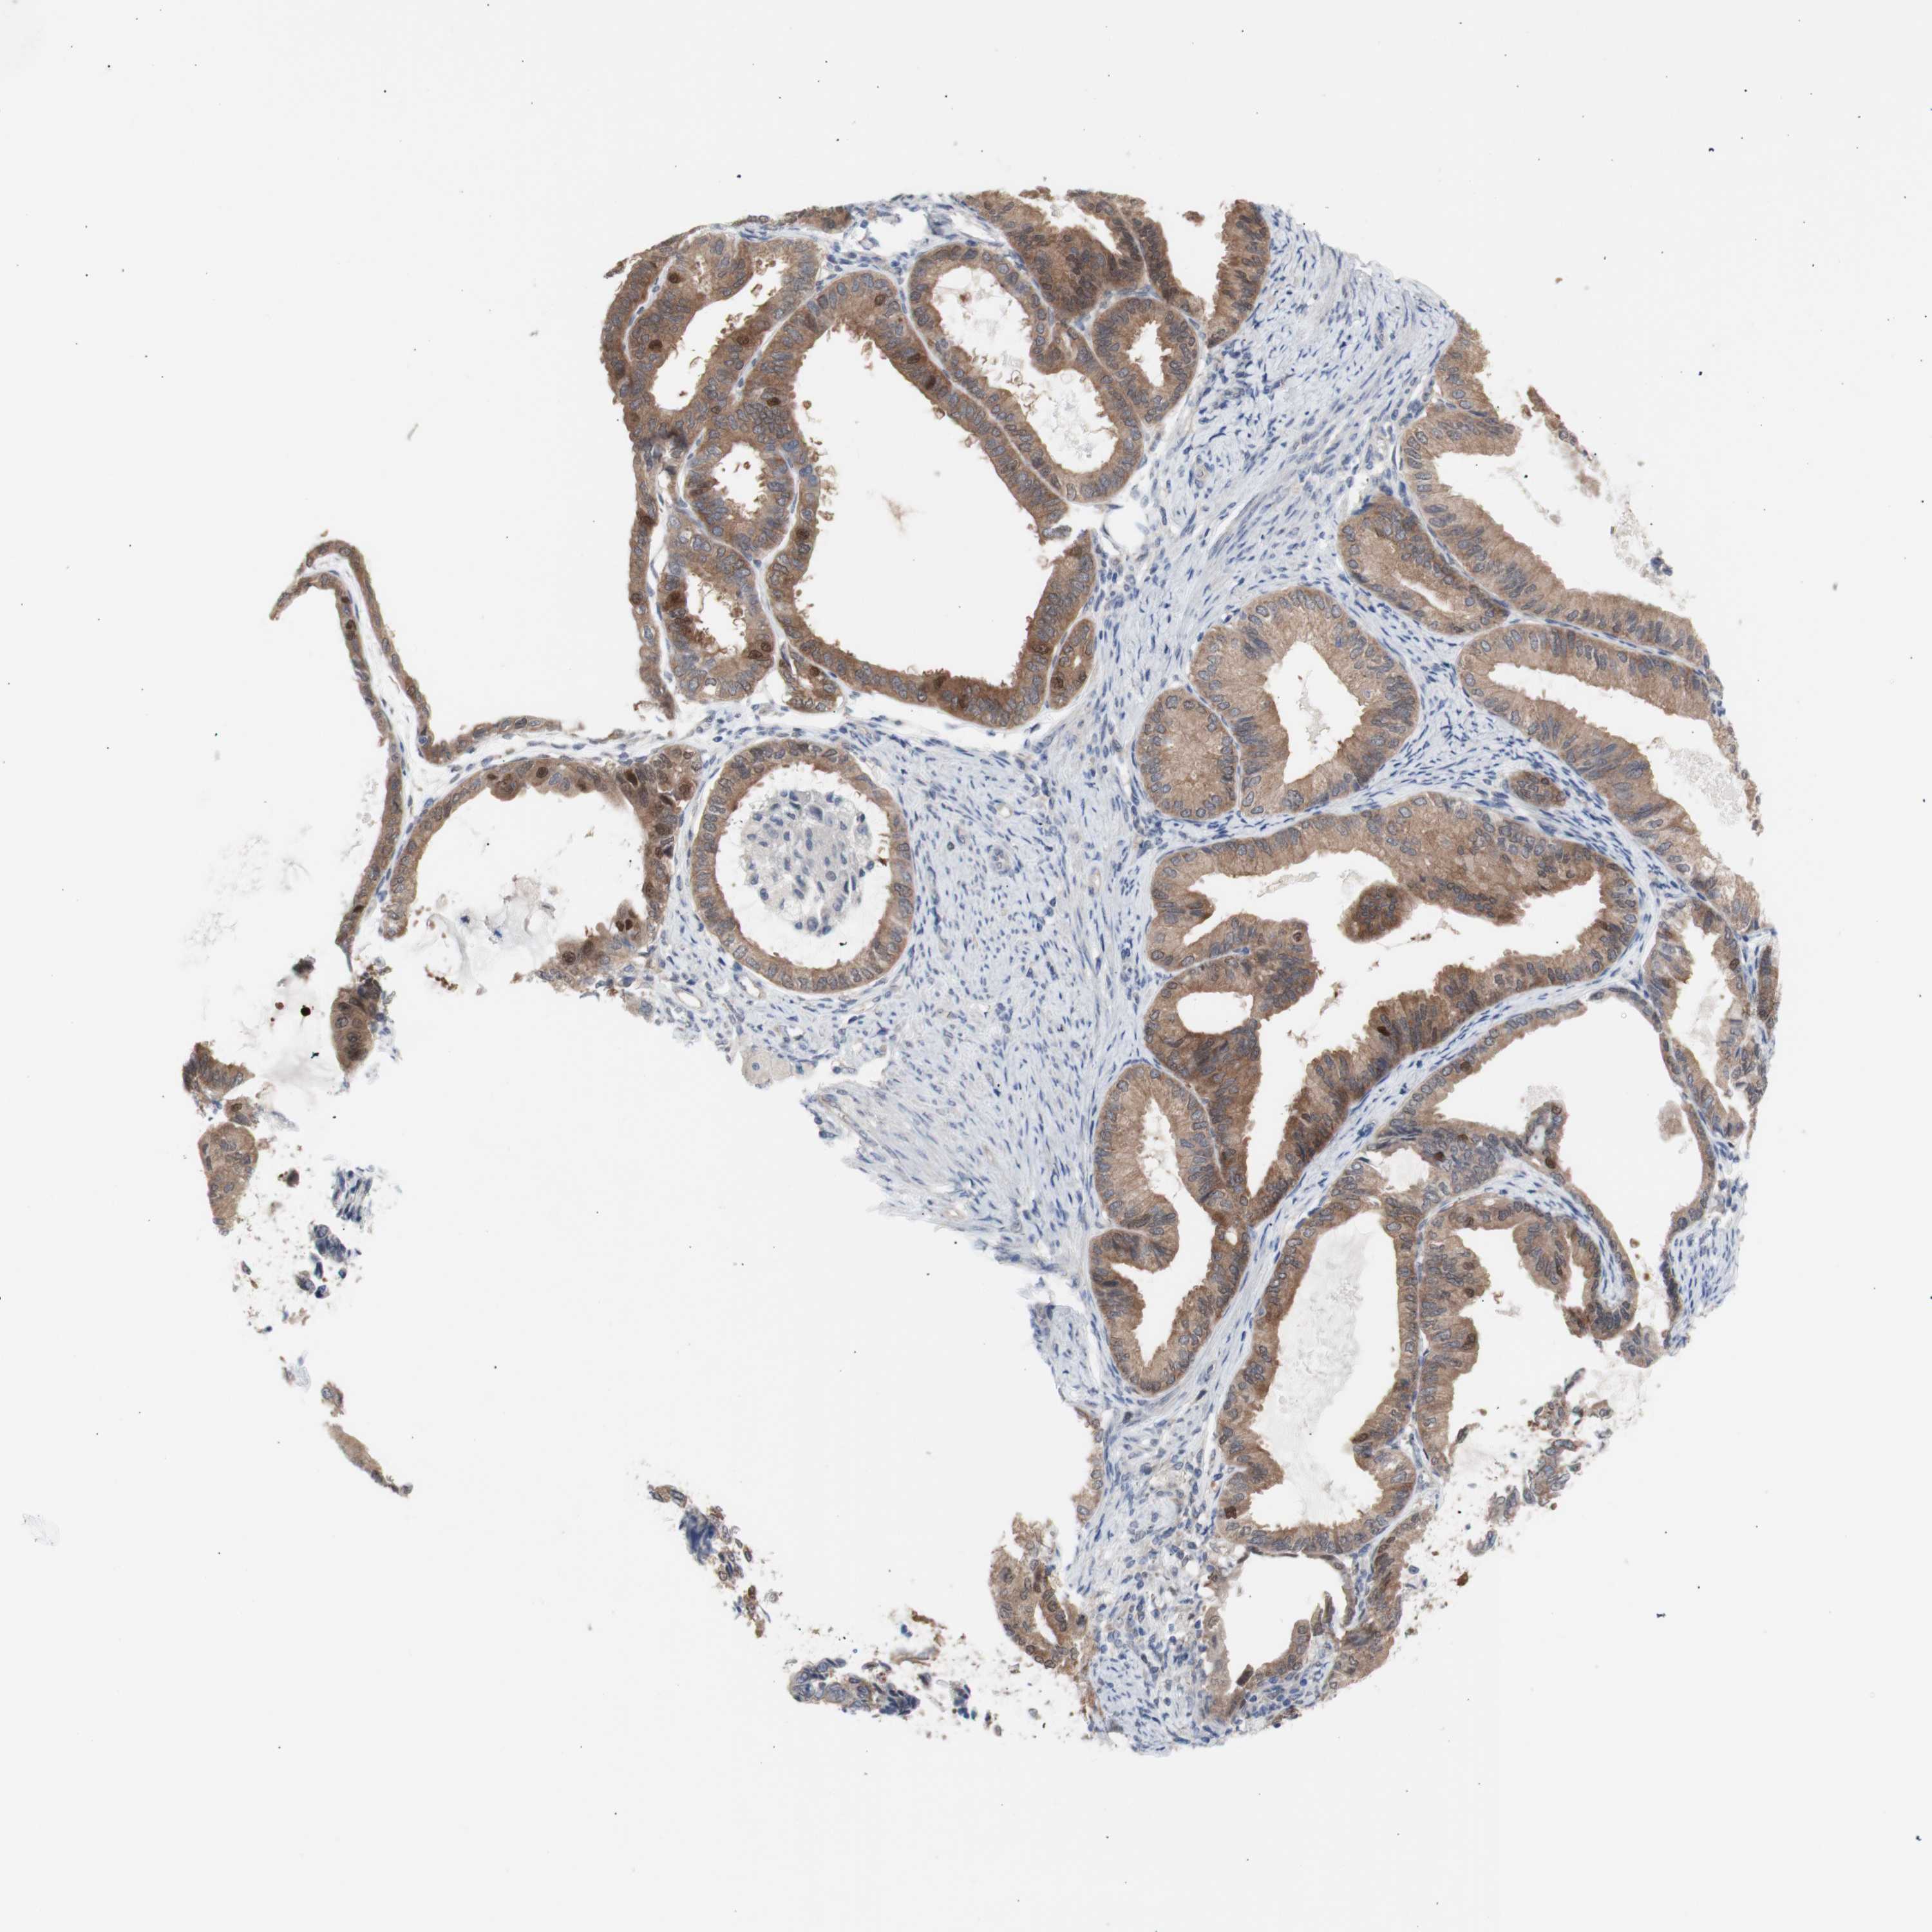

ENDOMETRIAL CANCER - Protein expressioni

A mouse-over function shows sample information and annotation data. Click on an image to view it in a full screen mode. Samples can be filtered based on level of antibody staining by selecting one or several of the following categories: high, medium, low and not detected. The assay and annotation is described here.

Note that samples used for immunohistochemistry by the Human Protein Atlas do not correspond to samples in the TCGA dataset.

Antibody stainingi

Antibody staining in the annotated cell types in the current human tissue is reported as not detected, low, medium, or high, based on conventional immunohistochemistry profiling in selected tissues. This score is based on the combination of the staining intensity and fraction of stained cells.

Each image is clickable and will lead to virtual microscopy that enables deeper exploration of all samples and also displays staining intensity scores, fraction scores and subcellular localization as well as patient and tissue information for each sample.

Antibody HPA005525

Antibody HPA064708

Antibody CAB012459

Staining

High

Medium

Low

Not detected

Intensity

Strong

Moderate

Weak

Negative

Quantity

>75%

75%-25%

<25%

None

Location

Nuclear

Cytoplasmic/membranous

Cytoplasmic/membranous,nuclear